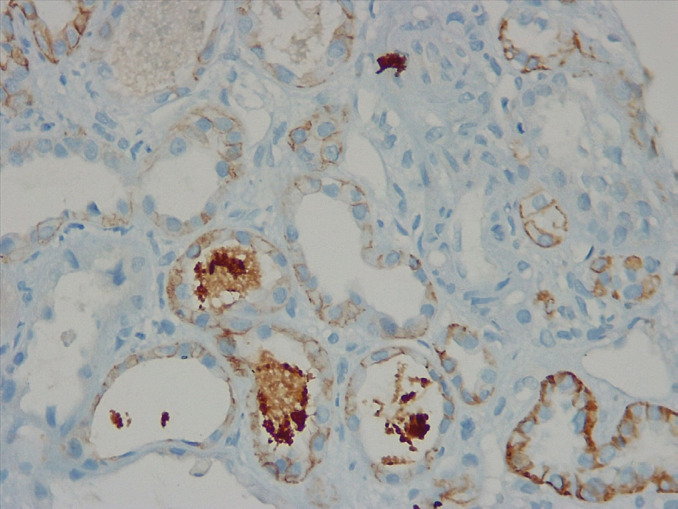

甲状腺功能障碍以多种方式影响肾脏。在病例报告中,甲状腺功能减退被描述为肾功能障碍的一个原因,一些大规模的流行病学研究显示甲状腺功能减退与肾功能参数异常有关。治疗甲状腺功能减退也有肾功能恢复和改善的报道。我们强调两个病例,其中甲状腺功能减退导致肾功能不全和治疗甲状腺功能减退导致肾功能改善。

Dysthyroid state affects kidneys in multiple ways. Hypothyroidism has been described as a cause of renal dysfunction in case reports, and a few large-scale epidemiological studies have shown association of hypothyroidism with abnormalities of renal function parameters. Restoration and improvement in renal functions have also been reported with treatment of hypothyroidism. We highlight two cases where hypothyroidism contributed to renal dysfunction and the treatment of hypothyroidism led to improvement in renal function.